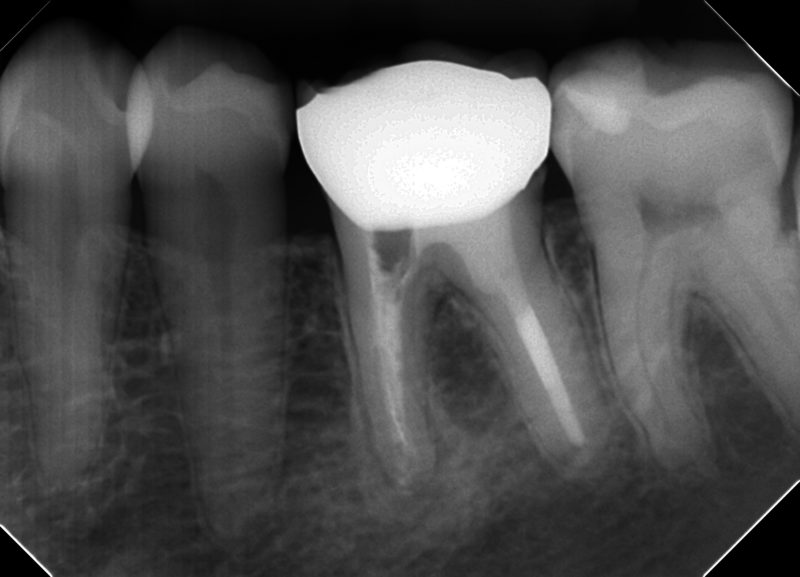

患歯は左下第一大臼歯

根管治療専門医にリトリートメント(根の治療の再治療)をしてもらったら、近心根にファイルが折れてしまったとのこと。

破折ファイルを除去するためなのか、歯質の削除量が多く分岐部にはストリップパーフォレーションに際どい状態でした。

根管の形態はVertucci TypeⅡいわゆるY字型で、根管内には根管充填剤やデブリがたくさん残っていました。